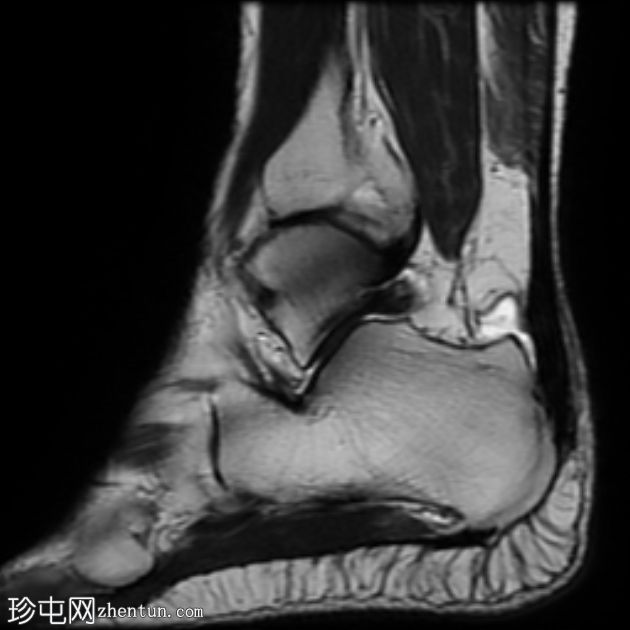

MRI

矢状位

T1

T2

STIR

跟腱插入

,伴有跟腱明显增厚,可诱发异常信号、跟腱后滑囊炎、跟骨后突及骨髓水肿信号。

Haglund综合征的检查结果令人印象深刻。

Haglund综合征是指以下三联征(Haglund三联征):

跟腱插入性病

跟腱后滑囊炎

Haglund畸形(即跟骨后上外生骨疣)